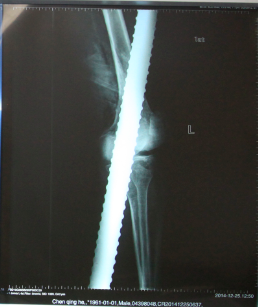

北京积水潭医院急诊的大夫和护士迅速对病人进行抢救,心电监护,开放静脉,并将患者左腿上的裤子小心翼翼的剪开。创伤骨科孙旭大夫和手外科童德迪、薛云浩大夫一边了解病人的情况,一边给病人进行检查,病人左脚没有知觉,怀疑至少有一根神经有损伤,为判断是否有骨折,拍了X光片子。

麻醉成功后,手外科童德迪医生慢慢将钢筋拔出,钢筋从膝关节穿过去,股骨下端和胫骨都劈断了,因伤势严重,术中要探查和修补血管和神经,最后上外固定架,手术进行了2个多小时,经过全体医护人员的努力,病人救治成功。

X光片